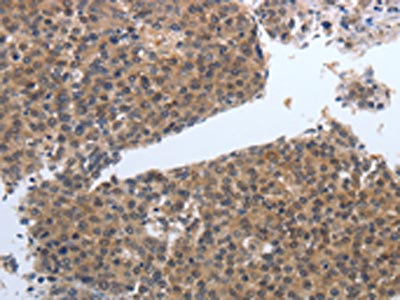

The image on the left is immunohistochemistry of paraffin-embedded Human liver cancer tissue using CSB-PA911363(PDGFB Antibody) at dilution 1/40, on the right is treated with synthetic peptide. (Original magnification: ×200)

The image on the left is immunohistochemistry of paraffin-embedded Human ovarian cancer tissue using CSB-PA911363(PDGFB Antibody) at dilution 1/40, on the right is treated with synthetic peptide. (Original magnification: ×200)